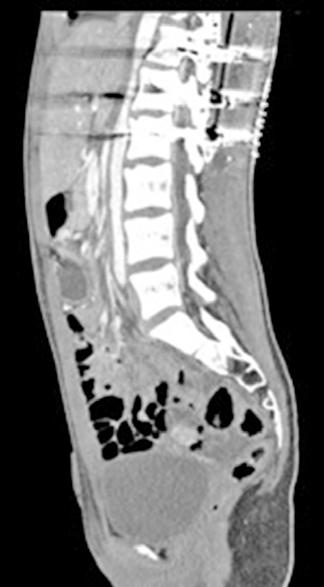

Figura 1 (A, B y C).

Imágenes de TC: Gran masa hepática localizada en segmentos VII, V y parte del IV. Signos de sangrado no activo.

A)Masa localizada entre VSH media y derecha.

B) Masa en contacto con rama portal.

C) Imagen en 3D donde se ve la gran masa y su relación con el resto del hígado.